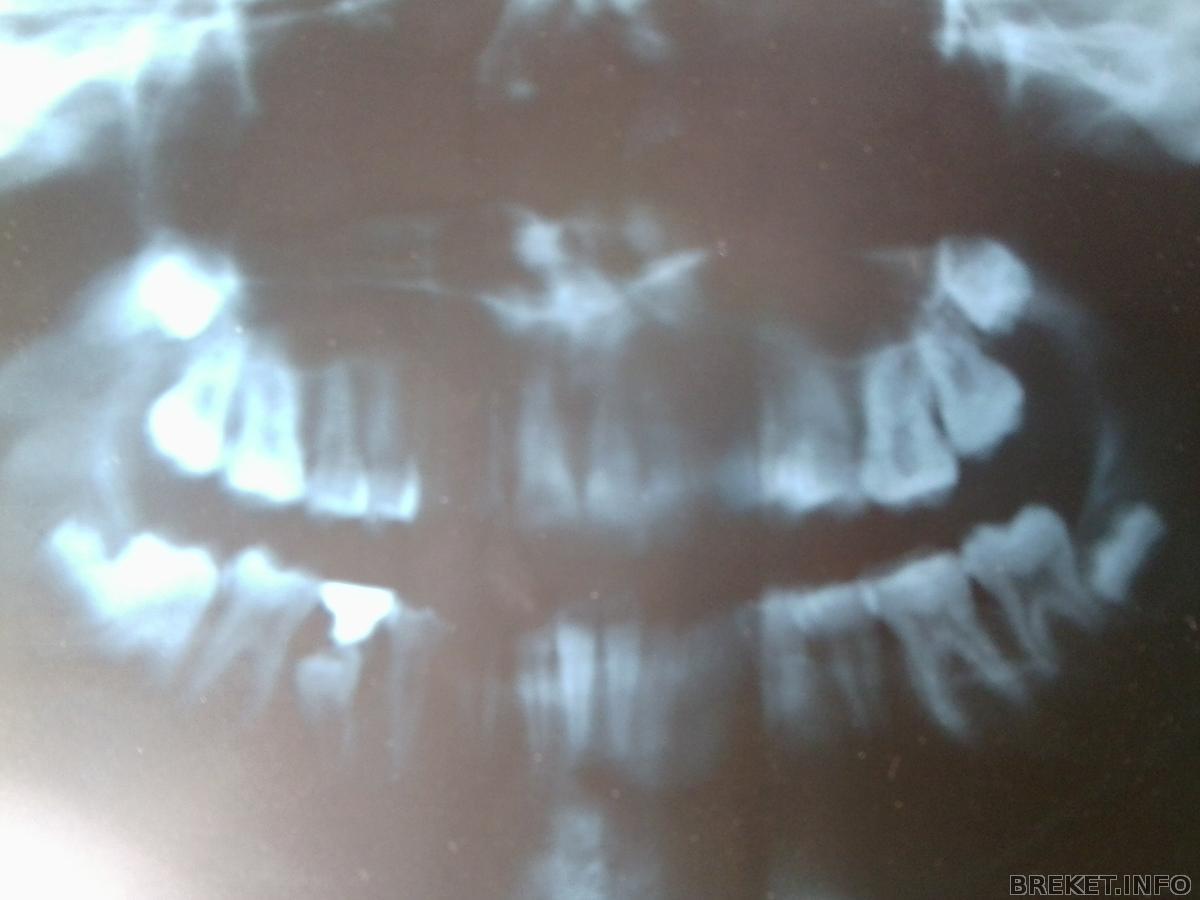

Только что вернулась от ортоши. Сказали что ставить бс пока рано, так как каналы ещё не закрылись. Сказали грызть много твёрдого. Не знаете сколько они закрываются? Прикиньте, в прошлый раз нас отпрвили гулять до лета, а теперь до зимы! Если поставить брекеты сейчас, потом зубы будут шататься и ничего с этим нельзя будет сделать. Буду ждать

А ещё у меня на нч пятёрка ещё не выросла. Поверх неё молочный зуб растёт. Если его удалить, 5ка может перестать расти. Вот такие вот дела.

А ещ она не ровная и если опять же вырвать молочный зуб, она может подпереть 6ку и та тоже наклонится.

Раз в несколько месяцев приказали делать рентген зубика, чтобы смотреть как он растёт. Ах да, ещё сказали что если выровнять зубы, расстояние между челюстями увеличится.